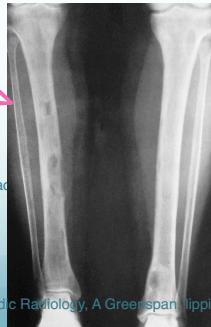

DEXA: Dual Emission X-ray Absorptiometry Demineralization of long bones, Pathological fracture

Lytic lesions caused by hyperparathyroidism are called Brown tumors. The term âBrown tumorâ is a misnomer because it is not a true neoplasm.